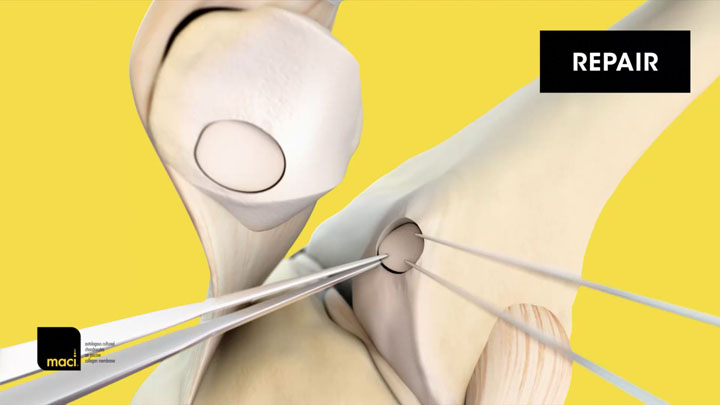

MACI® (autologous cultured chondrocytes on porcine collagen membrane) is an autologous cellularized scaffold product that is indicated for the repair of single or multiple symptomatic, full-thickness cartilage defects of the adult knee, with or without bone involvement.

MACI is intended for autologous use and must only be administered to the patient for whom it was manufactured. The implantation of MACI is to be performed via an arthrotomy to the knee joint under sterile conditions.

The amount of MACI administered is dependent upon the size (surface in cm2) of the cartilage defect. The implantation membrane is trimmed by the treating surgeon to the size and shape of the defect, to ensure the damaged area is completely covered, and implanted cell-side down.